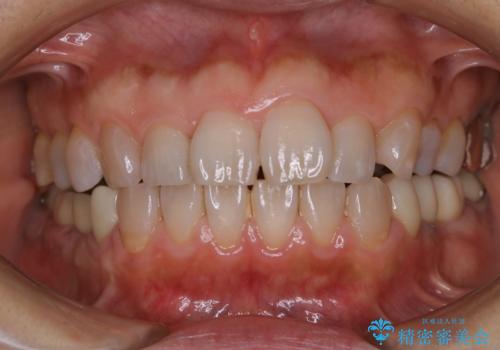

口臭予防のため歯科医院での歯の掃除 PMTC

- 口臭予防のためクリーニングをしたいとのことで来院されました。PMTC60分コースを行いました。

PMTC(自費クリーニング)60分コースを行いました。

PMTCで、バイオフィルム(細菌の塊)を破壊し、歯の表面をツルツルにすることでお口の中の細菌数を減らし歯周病のリスクが定着するのを防ぎます。更に、歯に新しい汚れがつきにくい状態になります。

バイオフィルムが除去されると、ご自身本来の歯の表面になります。PMTCをすることで口臭予防にもなり、定期的に行うことが大切です。